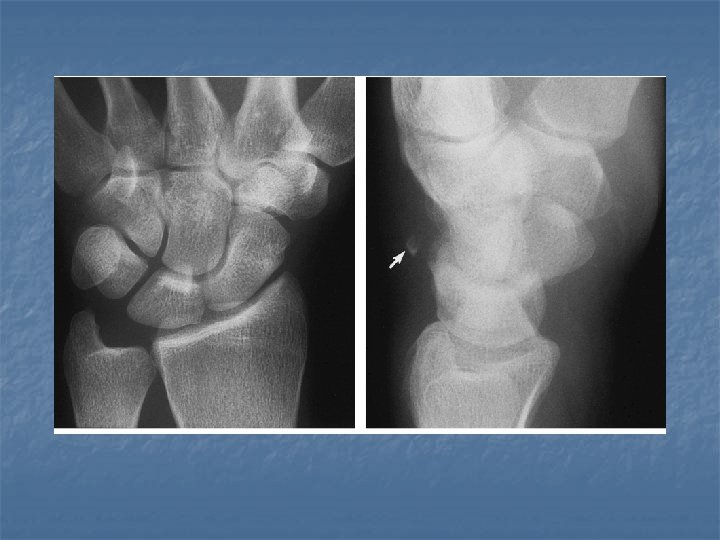

Perilunate dislocation n On lateral view: Dorsal or volar dislocation of the capitate. n Lunate remains in articulation with the radius although there may be some degree of tilt n n On dorsovolar view Crowdening of the proximal and distal carpal rows n Break in arcs II and III at the site of the capitate n

Lunate dislocation n On lateral view Axis of lunate is titled away from the articular surface of radius (spilled tea cup sign) n Capitate remains in normal alignment with radius and 3 rd metacarpal n n On dorsovolar view n Disruption of arc II while arc III remains intact